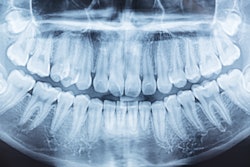

There may be a significant association between decayed, missing, and filled teeth (DMFT) index scores and a bone mineral density (BMD) diagnosis, according to a study published in BMC Oral Health.

Oral health was evaluated using the DMFT index and oral hygiene index-simplified (OHI-S) scores. Participants were grouped based on the number of surviving teeth, with low (< 20) and high (≥ 20) categories, they wrote.

The researchers found a statistically significant association between DMFT index scores and BMD diagnosis (F-statistic = 8.125, p < 0.001). The difference was most pronounced in the osteoporosis group compared to the other two groups. DMFT index scores were highest in the osteoporosis group (18.69) and lowest in the normal group (14.08, p < 0.001).

While the number of remaining teeth was lower in the osteoporosis and osteopenia groups than in the normal group (p < 0.001), the osteopenia group had a count closer to the normal group but significantly higher than the osteoporosis group. The group with the fewest remaining teeth also had lower total hip T-scores and significantly higher DMFT index scores (p < 0.001), they wrote.

"Tooth loss and dental decay rates were significantly high in patients with osteoporosis," they concluded.